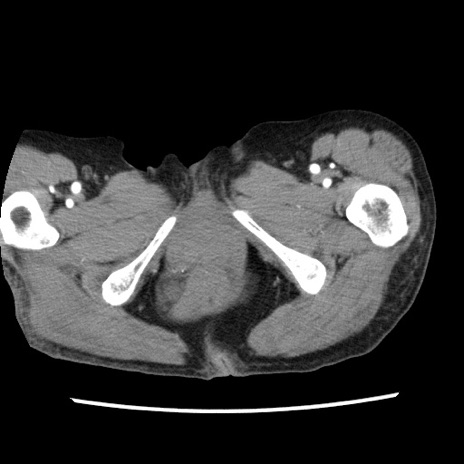

【症例】80歳代女性

【主訴】腹痛

【現病歴】8時間前から腹痛あり来院。

【既往歴】糖尿病、脂質異常症、子宮体癌にて子宮全摘術

【身体所見】意識清明・会話良好だが腹痛で苦悶様、全腹部にわたって反跳痛と圧痛あり

【データ】WBC 13600、CRP 0.14、LDH 224、CK 90